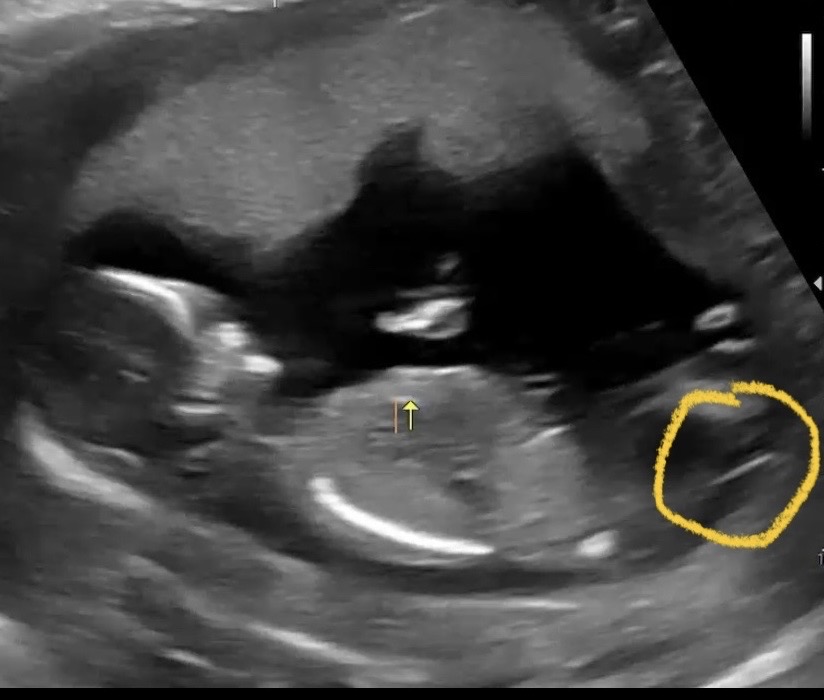

13주5일 오줌싸는 태아 아들일까요??

이렇게 오줌싸더라도 딸일 수도 있는거죠?? 각도법이 애매한거같아서요.